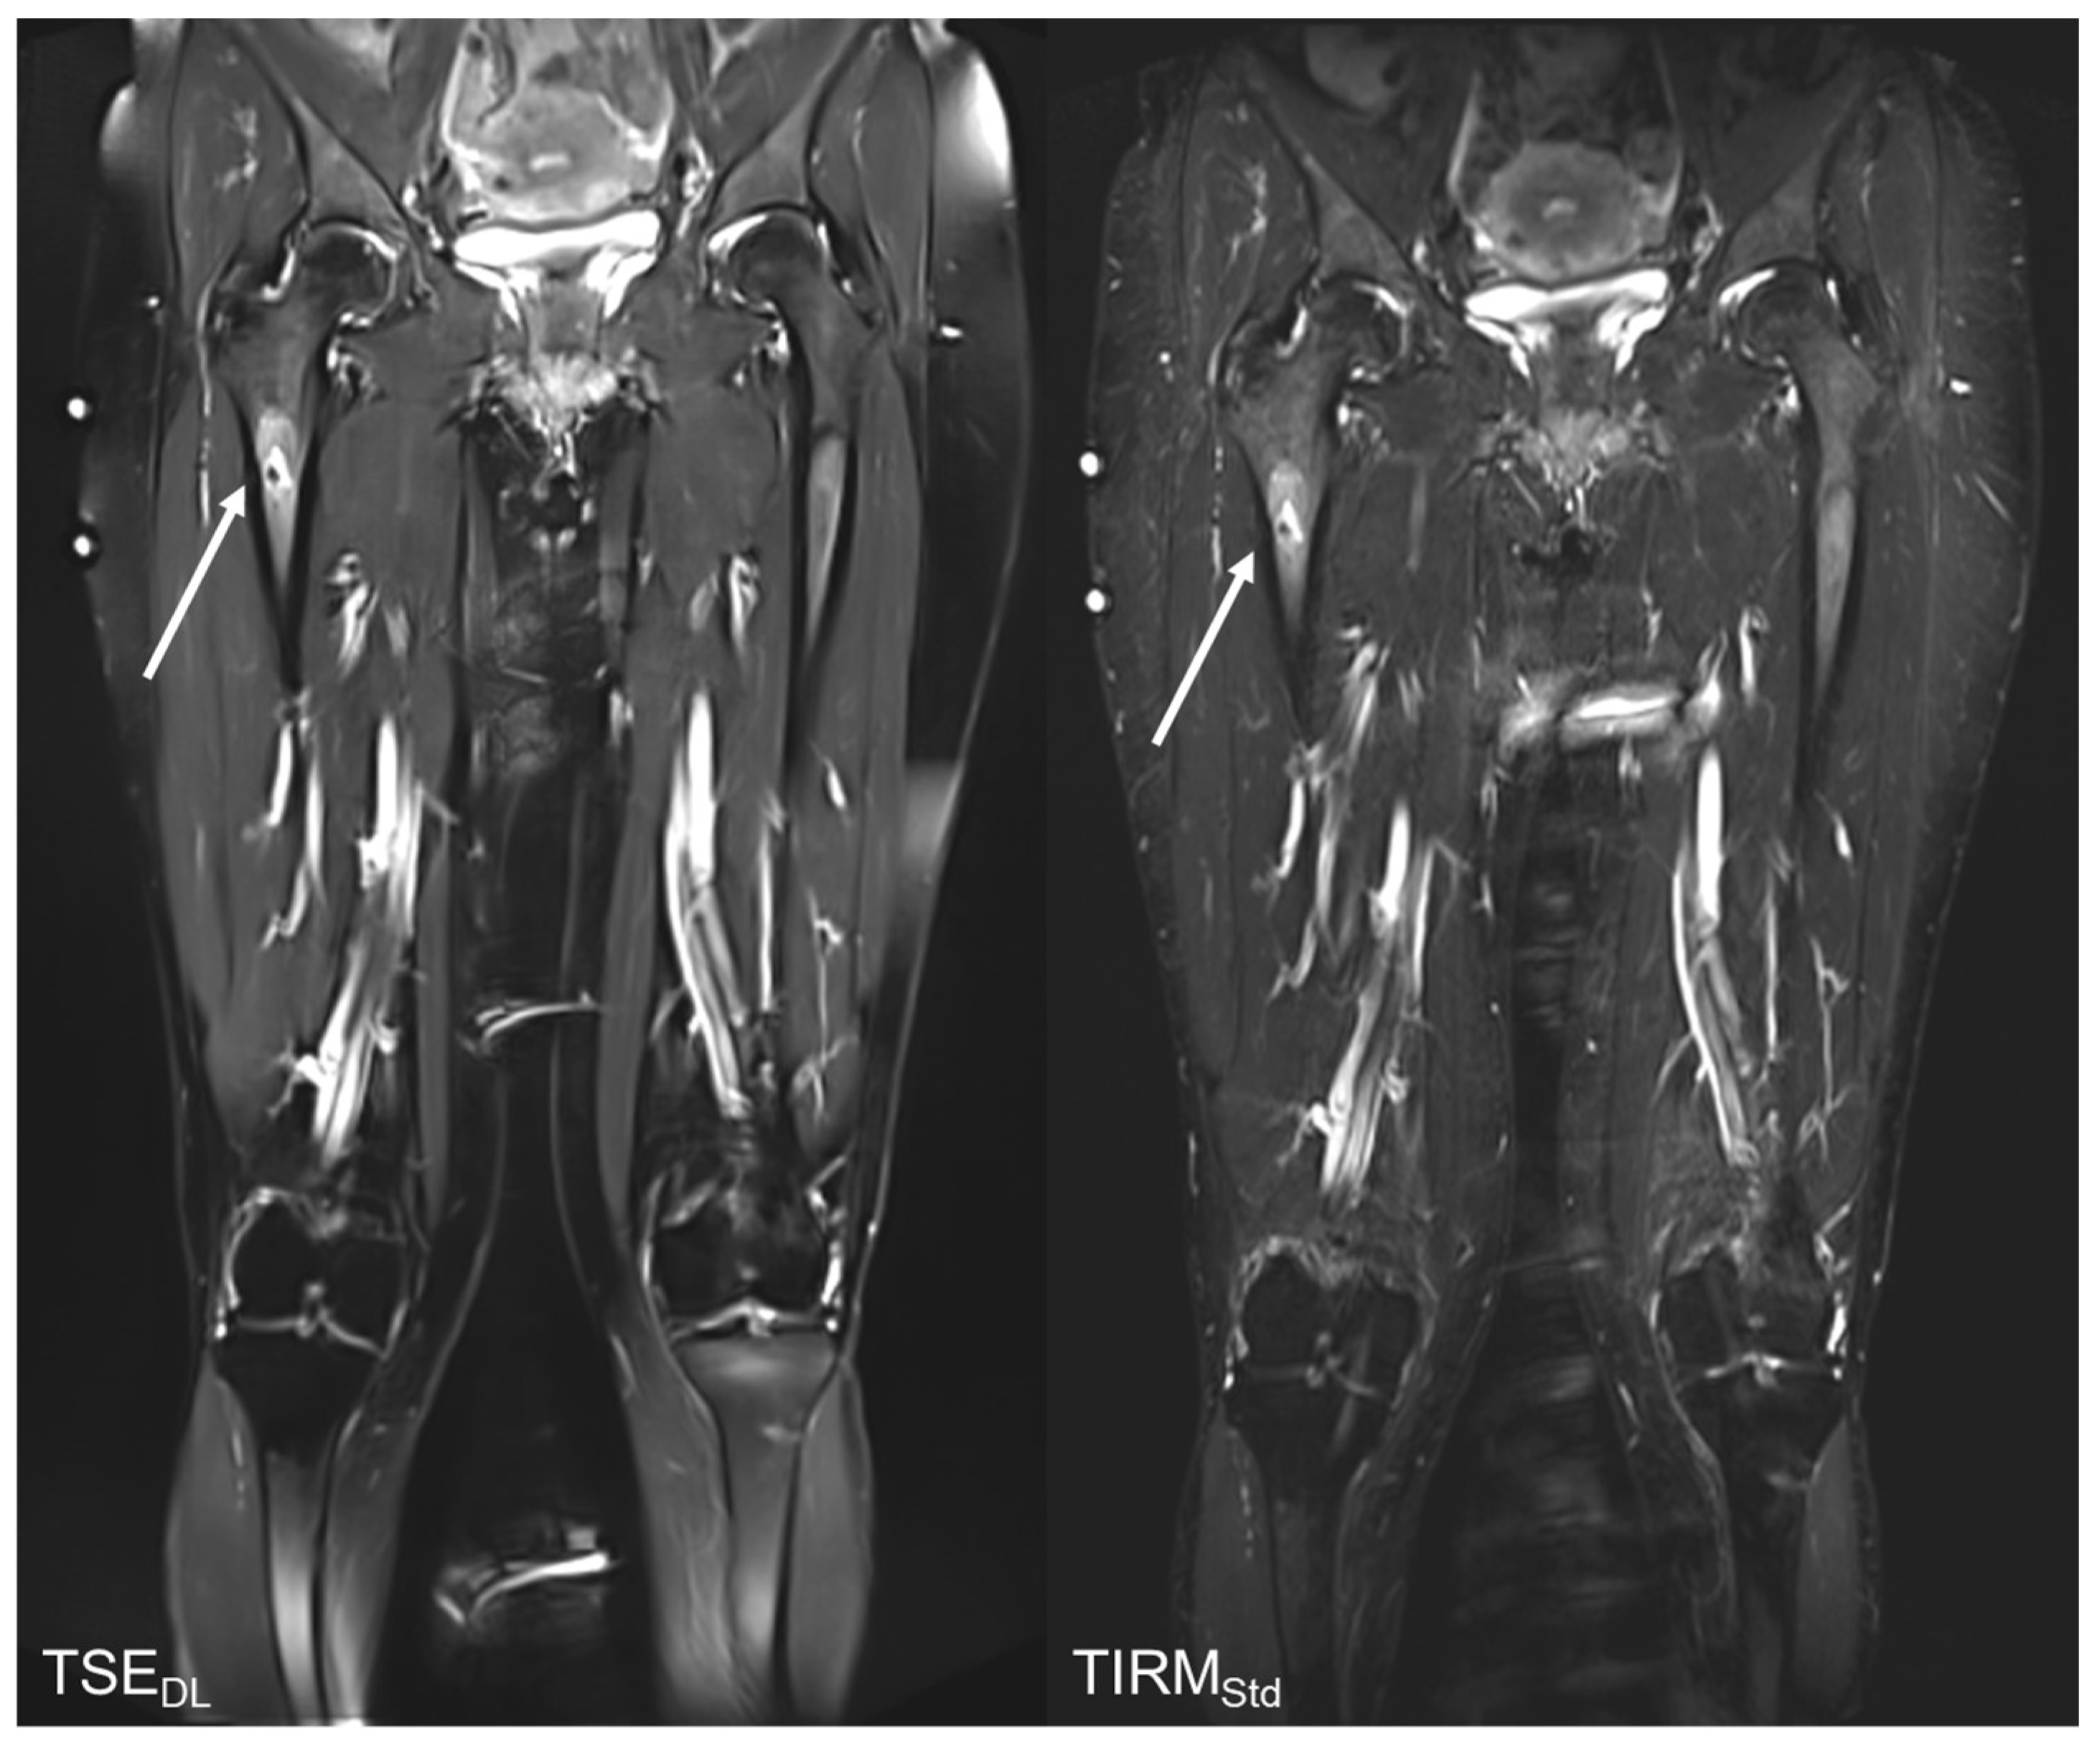

Reduction in Acquisition Time and Improvement in Image Quality in T2-Weighted MR Imaging of Musculoskeletal Tumors of the Extremities Using a Novel Deep Learning-Based Reconstruction Technique in a Turbo Spin Echo (TSE) Sequence

3.4. Qualitative Image Analysis

3.5. Subgroup Analysis